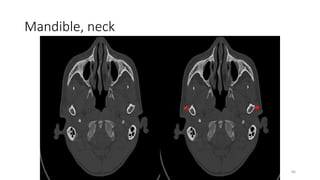

Mandible, neck

80